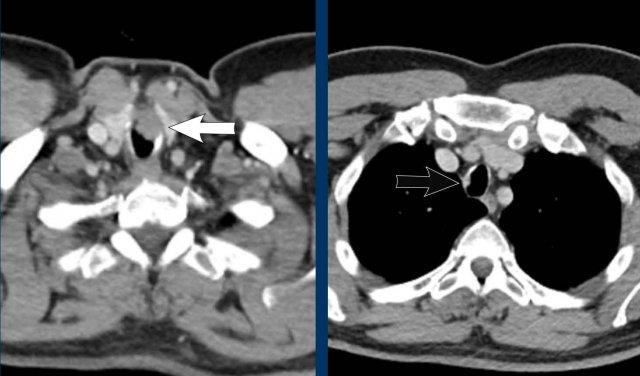

Hình ảnh

Phế quản khí quản tình cờ phát hiện ở nam giới 28 tuổi được chụp CT theo dõi ung thư (hình ảnh mặt cắt ngang) và ở nam giới 77 tuổi được chụp CT trong bối cảnh chấn thương (hình ảnh mặt cắt vành).